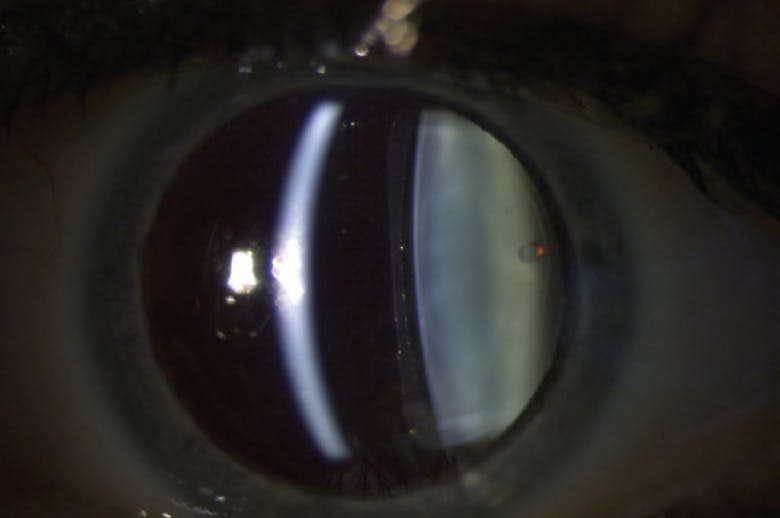

Management of patients with the Visian ICL requires a slightly different approach. For example, the Visian ICL will most often be placed in the posterior chamber and should have a vault between 250 µm and 750 µm over the crystalline lens.9 The vault can easily be estimated at the slit lamp using an optic section beam and comparing it to the thickness of the cornea (Figure 3).